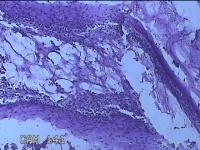

胎盘组织

孕2产39周LOP剖宫产单活胎男婴 剖宫产术

停经39周,下腹胀痛1小时。

灰白暗红色胎盘组织18x16x2.8㎝一个,表面光滑,血管清晰,颜色发暗,绒毛面结节状,轻度糜烂,表面有少许凝血块,切面见绒毛内有部分淤血,边缘蜕膜可见多个小血肿,脐带21.5x2x0.8㎝,切断脐带,见脐血管内有凝血块。